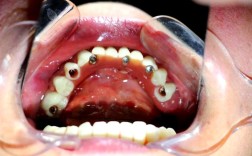

牙龈形态变化:术后1周左右,伤口缝线会被拆除,牙龈逐渐愈合,种植体基台(连接种植体和牙冠的部分)暴露后,牙龈会围绕基台形成“袖口”样结构,类似天然牙的牙龈形态,若牙龈愈合不良(如红肿、萎缩),需及时就医进行修正。

临时牙使用:若种植方案中包含临时牙,此阶段可佩戴临时牙恢复部分咀嚼功能,但需避免咬硬物,临时牙可能不如最终牙冠密合,需注意清洁,避免食物残渣堆积。

骨结合完成后(通常术后3-6个月),种植体已与牙槽骨稳固融合,此时可安装永久牙冠,种植牙基本恢复天然牙的功能,但并非“一劳永逸”,仍需长期维护。